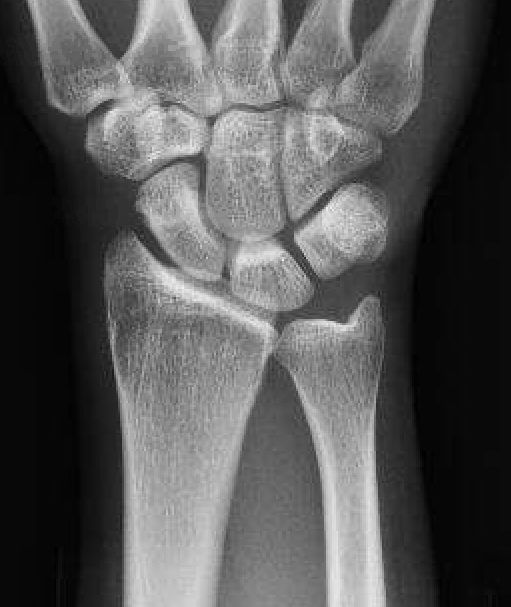

| Stage II | Stage IIIA |

|---|---|

| Sclerosis |

Collapse / fragmentation Normal carpal height |

![]() |